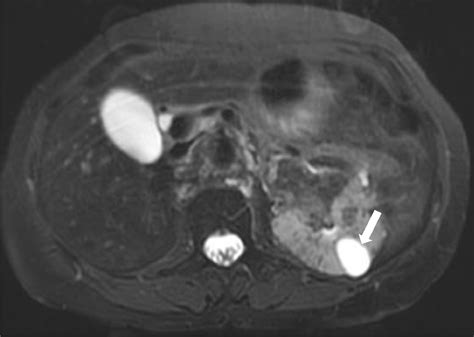

The central nervous system is frequently involved in TSC, leading to significant neurological morbidity, including epilepsy, cognitive impairment, and autism spectrum disorder. Imaging studies, particularly Magnetic Resonance Imaging (MRI), are the gold standard for evaluating these intracranial manifestations.

The hallmark brain lesions in Tuberous Sclerosis Radiology include:

• Cortical Tubers: These are areas of cortical dysplasia, appearing as hyperintense signals on T2-weighted and FLAIR MRI images. They are most commonly found in the frontal lobes.

• Subependymal Nodules (SENs): Small, benign nodules located along the walls of the lateral ventricles. They are often calcified and can be easily visualized on both CT and MRI scans.

• Subependymal Giant Cell Astrocytomas (SEGAs): These are tumors that typically arise from SENs near the foramen of Monro. Unlike static nodules, SEGAs have the potential for growth and can cause obstructive hydrocephalus, requiring urgent surgical or pharmacological intervention.

• White Matter Radial Migration Lines: These appear as linear bands of hyperintensity extending from the periventricular region toward the cortex, representing disrupted neuronal migration.